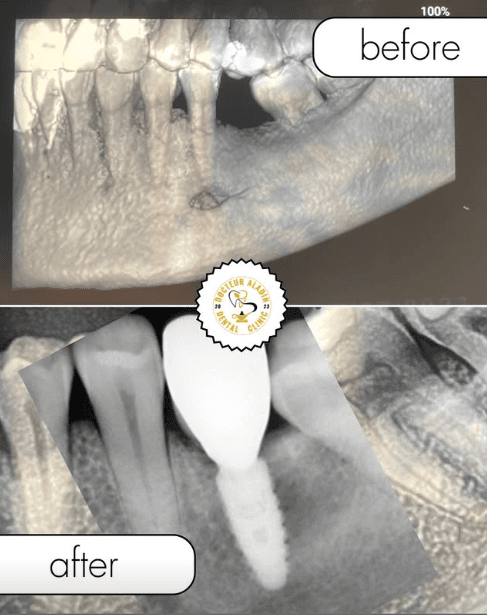

Before / After Results

Discover our patients transformations